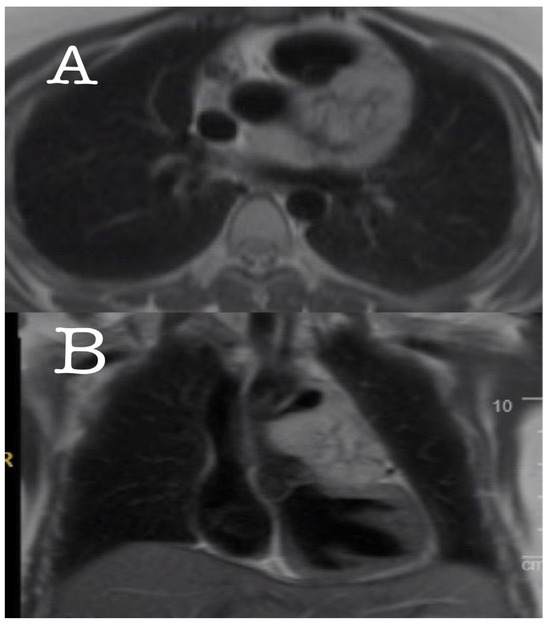

For further details, a computerized tomography (CT) angiography was performed, which showed a highly vascularized mass (size: 7.5 × 4.1 cm) encasing the LAD and the proximal LCX. Magnetic resonance imaging (MRI) of the chest also revealed an area of central necrosis within the mass (Figure 2 and Figure 3). Moreover, a left heart catheterization was performed and showed a sub-totally occluded left main coronary artery with 90% obstructed LCX. Laboratory investigations revealed an increased serum level of normetanephrine (3.21 nmol/L, normal range is less than 0.9 nmol/L) with a high chromogranin A level (859 nmol/L, normal range 0–6.0 nmol/L), which were suggestive of a paraganglioma tumor. The genetic was performed and resulted as positive for mutations in the succinate dehydrogenase gene (SDHx); one pathogenic variant, c.725G>A; p.Arg242His, was detected in the SDHB gene by massively parallel sequencing. This result is consistent with a diagnosis of hereditary paraganglioma–pheochromocytoma syndrome; clinical manifestations are variable. This individual’s offspring have a 50 percent chance of inheriting the pathogenic variant.

Figure 2. Axial (A) and coronal (B) MRI showed a mass encasing the LAD and the proximal LCX.